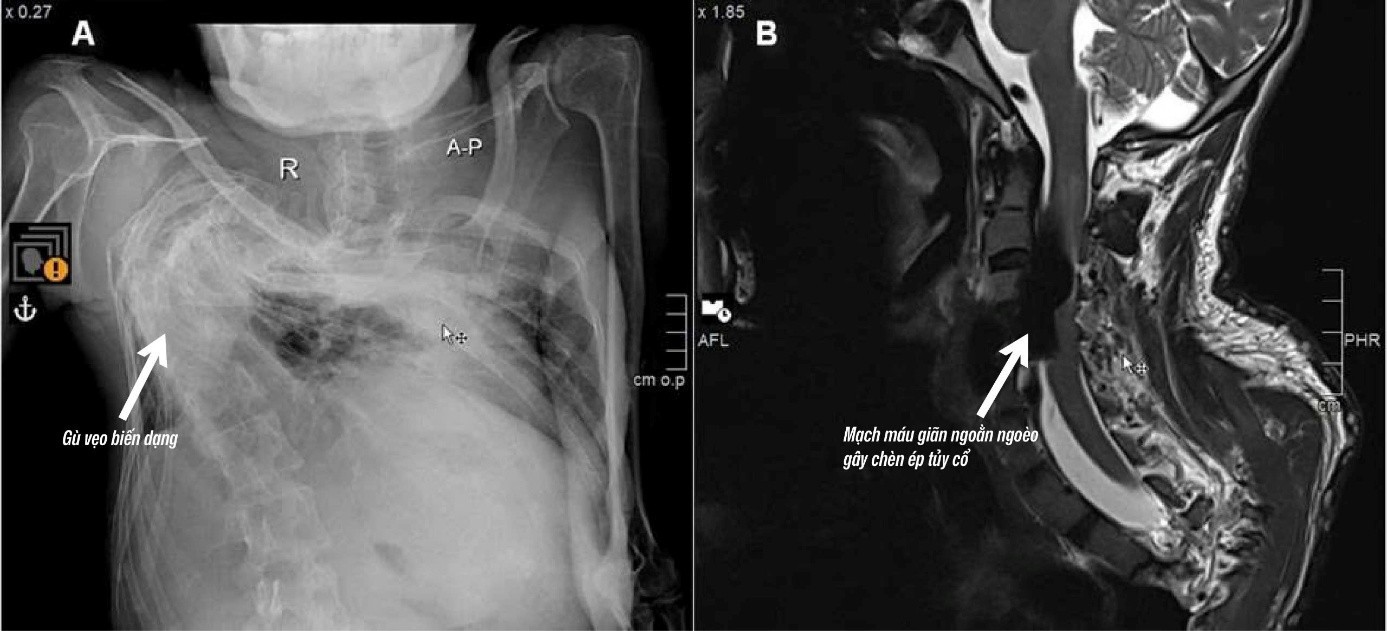

Từ nhỏ, anh N. đã mắc phải bệnh Von Recklinghausen, một rối loạn di truyền hiếm gặp với tỷ lệ mắc ước tính khoảng 1/3000 cá thể. Căn bệnh khiến cơ thể anh xuất hiện các u sợi thần kinh và dễ gây biến dạng xương khớp, gù vẹo cột sống.

Qua thăm khám và chụp MRI, bác sĩ phát hiện anh N. bị bệnh rò động tĩnh mạch vùng cột sống làm cho tĩnh mạch quanh tủy sống vùng cổ giãn ngoằn ngoèo, tạo thành một khối lớn gây chèn ép. Tình trạng này là nguyên nhân khiến anh N. bị yếu liệt tay chân, đau nhức và khó vận động. Bác sĩ nhận định, đây là một bệnh lý cực kỳ hiếm gặp.

Theo BS.CKI Trần Nguyễn Khánh – Đơn vị Can thiệp mạch DSA, Bệnh viện S.I.S Cần Thơ: "Trường hợp này phức tạp hơn nhiều so với thông thường vì cột sống biến dạng nặng, giải phẫu mạch máu bị thay đổi theo, khiến việc tiếp cận điều trị trở nên rất khó khăn."